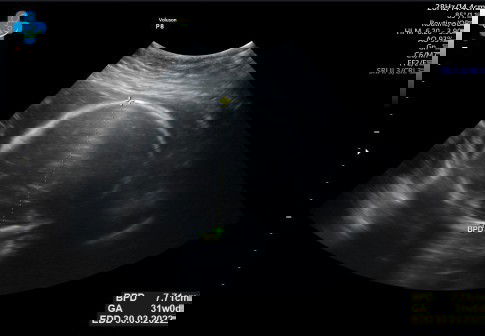

Mlm buibu.. Saya mau cerita sedikit nih, jd hpht saya 12 juli 2021 (usia kandungan saya skrg 28minggu), HPL 19 april 2022. Tadi siang saya priksa kandungan. Dan ternyata di usg, usia kehamilan saya mnjdi 31-32 minggu (HPL maju menjadi 30 maret 2022). Taksiran berat janin 1,6 kg. Apakah krna taksiran beratnya lebih besar dari berat normal usia kandungan saya ya, makanya usia kandungan jg jd lebih tua dan HPL maju smpe 3 minggu? Adakah yg punya pengalaman sama buibu? Apakah lahirannya maju dari hpl awal?#bantusharing